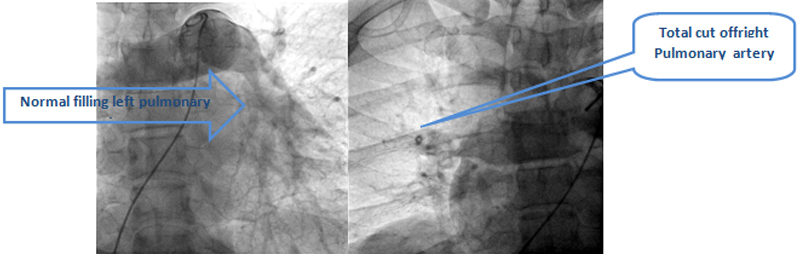

Diagnosis was confirm by pulmonary angiography which revealed total cut off of right side of pulmonary artery due to large thrombus and complete occlusion of his brachial-axillary artery by large thrombus. Looking to literature and available scientific evidence, the preferred treatment of choice of the patient with massive pulmonary embolism is systemic thrombolysis.